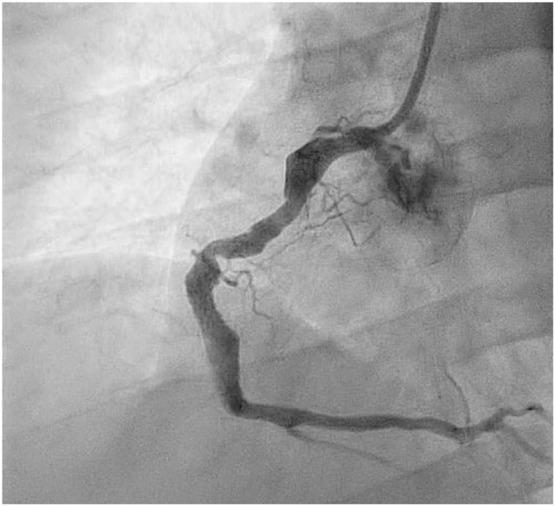

Coronary artery ectasia (CAE), also known as aneurysmal coronary artery disease, is defined as an abnormal diffuse (ectasia) or segmental (aneurysmal) dilatation of any branch of the coronary arteries. It is a well-recognized entity with 1.2-4.9% prevalence. Our case is a 46 year old male with no prior medical problem who presented to the ER with inferior ST elevation myocardial infarction (STEMI). The Coronary angiogram revealed multiple ectatic segments in the right coronary artery (RCA) with 100% stenosis in the middle segment. Upon wiring the RCA a big clot burden was noted on the ectatic segment. We planned to keep him on aggrastat infusion for 24 hours then re-cath him. The second cath showed complete resolution of the clot and the lesion was stented with drug eluting stent showing excellent final result. We found that our case is interesting and unique in exploring the association of CAE that presents with STEMI and how to treat it safely in the cath lab, knowing that CAE is an uncommon finding during coronary angiography. CAE is associated with many coronary artery disease (CAD) risk factors and etiologies as well as pathologic progression. Patients with CAE are usually asymptomatic but can still present with symptoms of coronary artery occlusion. There is still no standard treatment specific for CAE itself, but when presenting with occlusive symptoms, management is guided by the extent of occlusion similar to CAD.

冠状动脉扩张(CAE),也被称为动脉瘤样冠状动脉疾病,被定义为冠状动脉任何分支的异常弥漫性(扩张)或节段性(动脉瘤样)扩张。它是一种公认的疾病,患病率为1.2%-4.9%。我们的病例是一名46岁男性,既往无病史,因下壁ST段抬高型心肌梗死(STEMI)就诊于急诊室。冠状动脉造影显示右冠状动脉(RCA)有多个扩张节段,中间节段有100%的狭窄。在对RCA进行导丝操作时,在扩张节段发现了大量血栓负荷。我们计划让他接受阿昔单抗输注24小时,然后再次进行心导管检查。第二次心导管检查显示血栓完全溶解,病变用药物洗脱支架置入,最终结果良好。我们发现我们的病例在探讨表现为STEMI的CAE的关联以及如何在导管室安全治疗方面既有趣又独特,因为CAE在冠状动脉造影中是一种不常见的发现。CAE与许多冠状动脉疾病(CAD)危险因素、病因以及病理进展相关。患有CAE的患者通常无症状,但仍可能出现冠状动脉闭塞症状。目前仍没有针对CAE本身的标准治疗方法,但当出现闭塞症状时,治疗方法与CAD一样,以闭塞程度为指导。